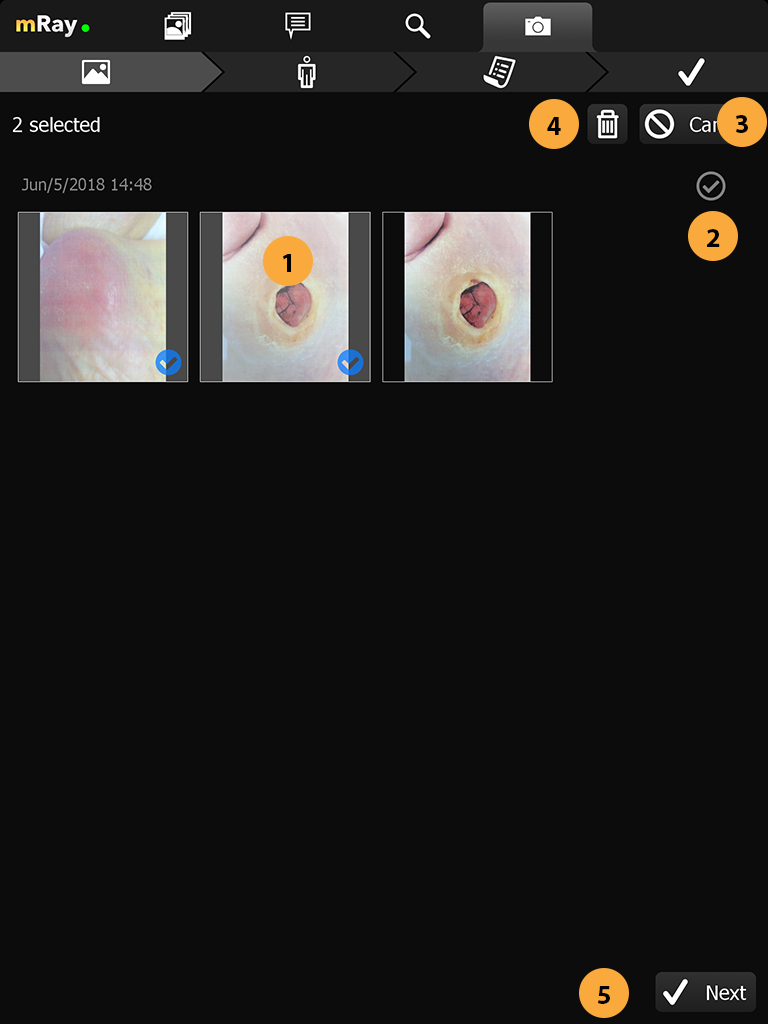

|

Danger

Be careful and do not delete images by accident. Deleted images can not be restored. |

If you want to inspect an image more detailed you can enter the photo view by clicking the target photo. Inside the photoview you get a fullscreen overview of the image. In this mode you can perform all the transform operations that are already known from the regular viewer (panning, zoom). By clicking the next or previous (Point 2) button you can navigate between the images.

-

Go back to the image gallery.

-

Switch between images. You can also use a swipe gesture to move forward / backward in the image stack.

-

Deletes the currently opened image. Deleted images can not be restored.

-

Shows the date and time the image was taken.